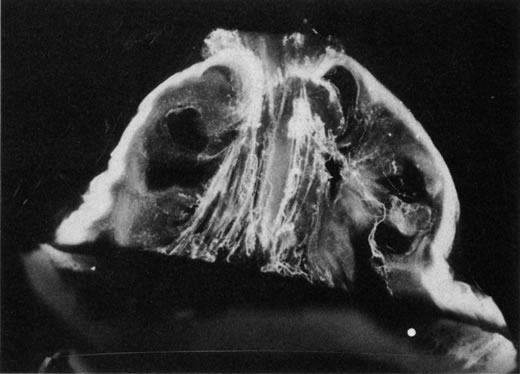

Fig. 9. Vitreomacular traction. Vitreous can remain attached to the macula even in the presence of posterior vitreous detachment. In such cases, vitreous can extrude through the premacular vitreous cortex and fibers can insert into the macula. B, C, and D are an artist's rendition of this phenomenon. A demonstrates vitreous extrusion into the retrohyaloid space in a specimen from a middle-aged human. (Adapted from Jaffe NS: The Vitreous in Clinical Ophthalmology. St. Louis, CV Mosby, 1969; and Jaffe NS: Vitreous traction at the posterior pole of the fundus due to alterations in the posterior vitreous. Trans Am Acad Ophthalmol Otolarynogol 71:642, 1967.)

Lindner111 and Jaffe112 described that in some cases of PVD, there is herniation of vitreous through the vitreous cortex of the posterior pole. As previously mentioned, Gartner67 drew an analogy between this phenomenon and the herniation of the nucleus pulposus in the intervertebral disks of the spine. When a PVD involves herniation of the vitreous into the retrovitreal space by way of the premacular vitreous cortex, there can be persistent attachment to the macula and traction (Fig. 9).113